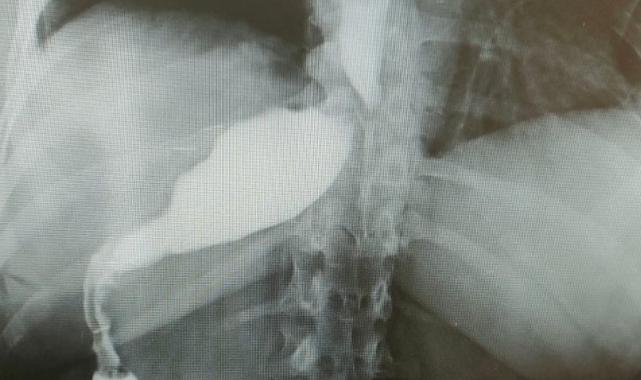

Almanya'dan tüp mide ameliyatı olmak için Antalya'ya gelen 46 yaşındaki hemşire Antje Kirscht, eşine az rastlanır bir tıbbi durumla karşılaştı. Antalya'da özel bir hastanede gerçekleştirilen operasyon sırasında Kirscht'in midesini olması gerektiği yerde göremeyen doktorlar kısa süren şaşkınlığın ardından mideyi karaciğerinin arkasında, sağ tarafta buldu. Mide başarılı bir operasyonla küçültülürken bu sıra dışı anatomik durumun, dünyada yalnızca 100 binde bir görüldüğü biliniyor.

Ameliyat esnasında cerrahi ekip, Kirscht'in midesini karaciğerinin arkasında, sağ tarafta buldu. Bu sıra dışı anatomik durum, hem hasta hem de ekibin şaşkınlık yaşamasına neden oldu.

Çok yapılan bu operasyonlar içerisinde hastanın değişik bir anomalisi vardı. 100 binde bir görüldüğü söyleniyor. Organların hepsi ters olabiliyor. Bu daha sık görülen bir şey ama bu hastada bütün organlar yerli yerinde ama sadece mide sağ tarafa kaymış. Yani karaciğerin arkasına gitmiş. Operasyona başladığımızda mideyi bulamadık. Karaciğeri kaldırınca mideyi sağ tarafta gördük. Bu çok nadir bir durum. 2023 yılı verilerine göre, böyle bir tüp mide ameliyatı dünyada yalnızca 50 kişiye uygulanmış. Biz de bu vakayı başarıyla gerçekleştirdik. Teknik açıdan bizi zorlayan ancak deneyimimizi artıran bir ameliyat oldu.

Prof. Dr. Gürkan, ameliyatın detaylarına değinerek, “Tüp mide operasyonunun ayna görüntüsünü yaptık. Normalde sol tarafta yaptığımız obezite ameliyatını bu hastada sağ tarafta gerçekleştirdik. Midenin karaciğerin arkasında olması ameliyat süresini 15 dakika uzattı ve toplamda 1 saat sürdü. Bizim için de hoş bir tesadüf oldu” diye konuştu.